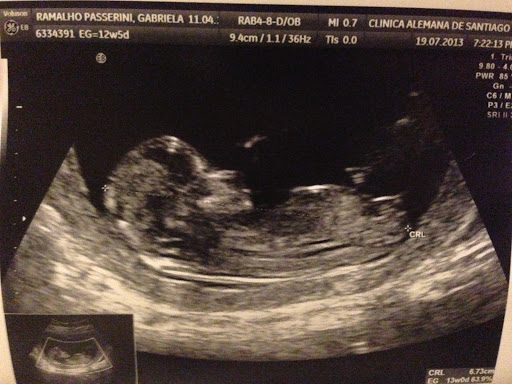

6- É logo depois de um ultra-som morfológico com um baby totalmente lindo, barrigudo, saudável e saltitante! Quer ver também?

| 6,73 cm de gostosura!!! |